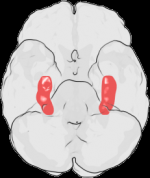

腦部的結構性破壞是可見的,生前酒精暴露會對腦部或其結構造成物理性破壞。結構性異常包括頭小畸形,或其他腦部結構異常,如胼胝體的發育不良、小腦發育不全。

在懷孕首3個月,酒精影響腦細胞的移行及組織,造成腦部的結構性畸形或缺憾。在第6-9個月,破壞可以延伸至負責記憶、學習、感情及將視覺與聽覺資訊編碼的海馬體,引起神經性及功能性的缺憾。

直至2002年,共有25個嬰兒屍體解剖個案是患有胎兒酒精綜合症。首宗個案發生於1973年,一個於出生後不久死亡的嬰兒。檢查發現有廣泛的腦部受損,包括有頭小畸形、移行異常、胼胝體發育不全及在左腦有大量的神經膠質與軟腦膜異位。

於1977年,另一個嬰兒於出生後十天死亡,其母親亦是酗酒的。屍體解剖顯示有嚴重的腦水腫、異常神經移行及細小的胼胝體與小腦。胎兒酒精綜合症都會與腦幹及小腦的改變、胼胝體及前連合發育不全、神經移行失誤、缺乏嗅球、脊髓脊髓膜膨出和孔洞腦畸形有關。